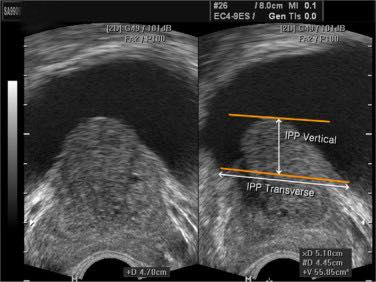

Hình ảnh này cho thấy các mức độ phì đại tuyến tiền liệt (BPH) trên siêu âm dựa trên thể tích tuyến tiền liệt và tình trạng lồi tuyến tiền liệt vào bàng quang (IPP):

Vì vậy, mức độ nghiêm trọng được xác định bởi cả thể tích tuyến tiền liệt và mức độ lồi vào bàng quang (IPP).